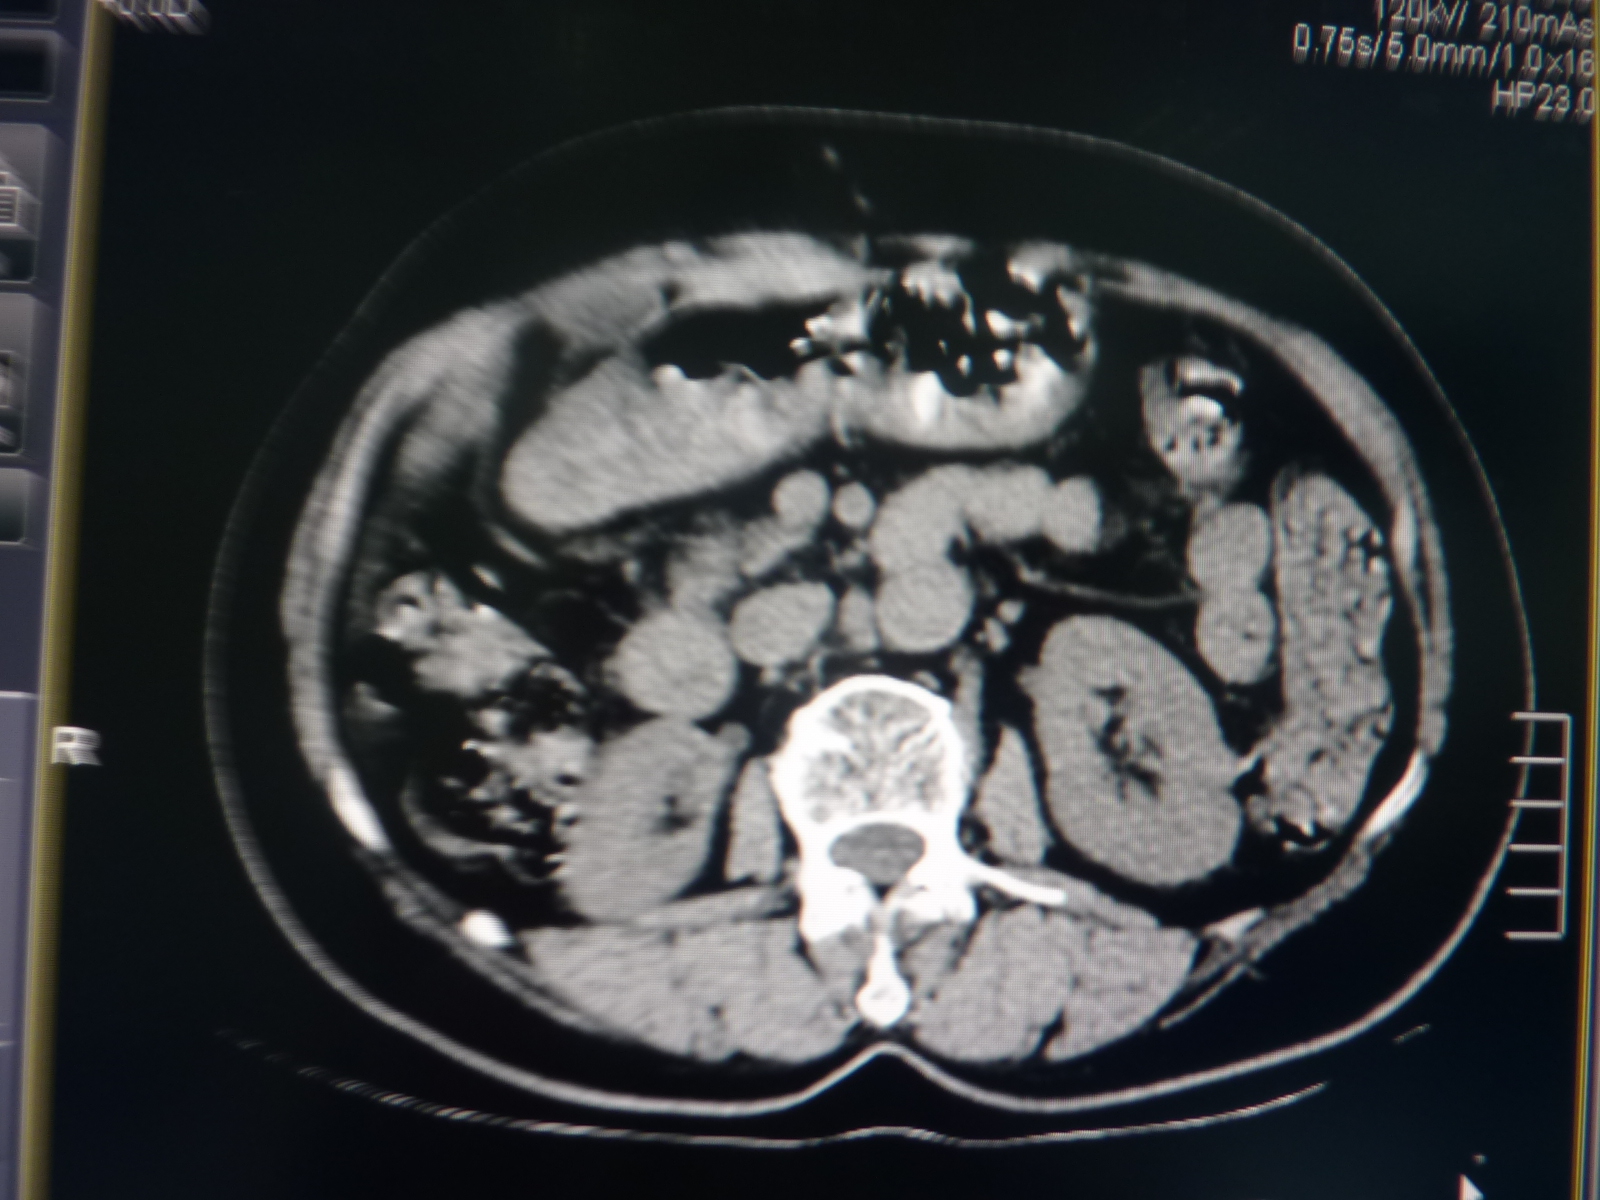

CT51668:80,糖尿病食欲减退

超声疑肝内占位?没看见病灶,脂肪肝,胆囊结石

既然超声疑肝内占位,那么,还是完善影像检查后,在定论吧,建议增强。